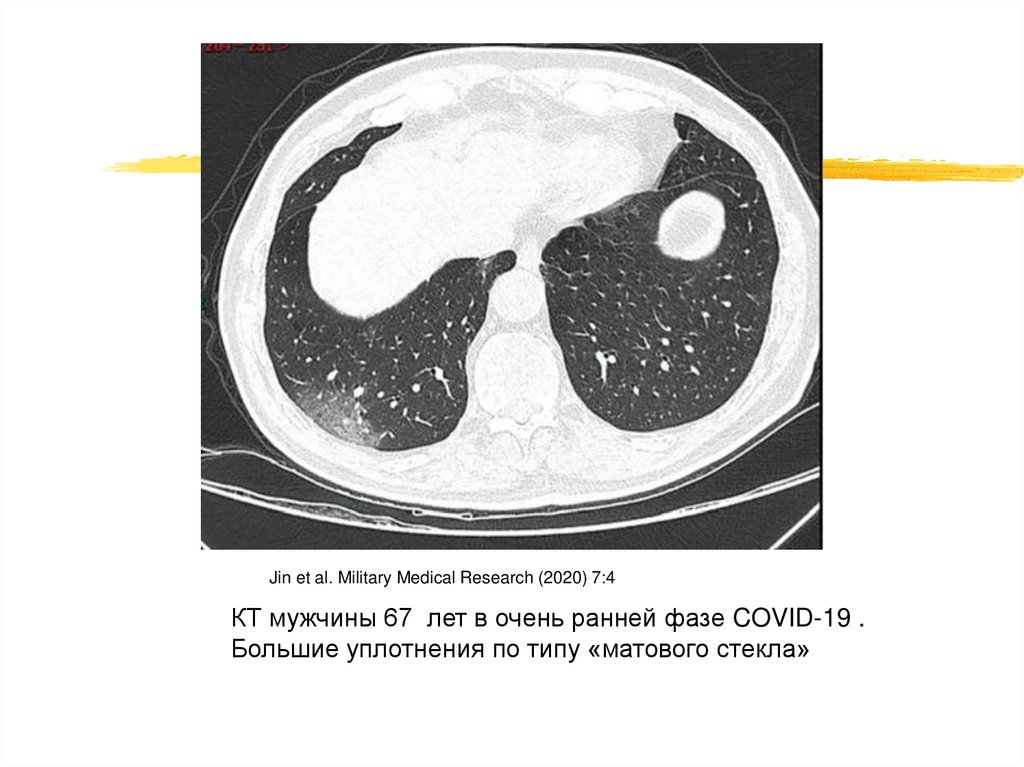

Jin et al. Military Medical Research (2020) 7:4

КТ мужчины 67 лет в очень ранней фазе COVID-19 .

Большие уплотнения по типу «матового стекла»